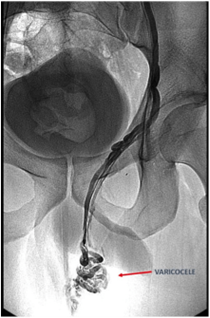

El paciente acudirá en ayunas a la sala de Radiología Vascular, que es un quirófano equipado con un angiógrafo, dispositivo que mediante el uso de rayos X permite navegar de forma controlada por dentro de los vasos y conductos del cuerpo. El radiólogo realizará la punción de una vena del brazo por donde entrarán los catéteres, navegará con el catéter hasta el varicocele y realizará la embolización del varicocele.

Embolización del varicocele